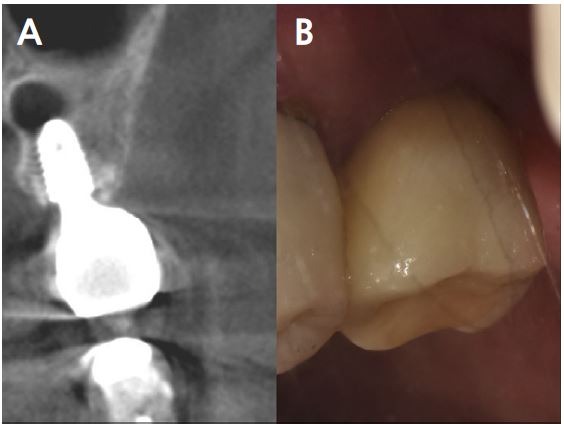

A 2-year follow-up CBCT view revealed that the condition was maintained without any complications for 21 months after prosthesis placement (Fig. 16A, 16B).

Follow-up CBCT view obtained after 2 years revealed that the bone and implant conditions were maintained without any complications for 19 months after prosthesis placement (Fig. 11A, 11B).